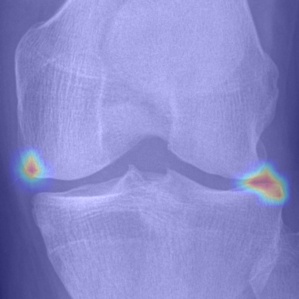

Refer to caption

(a) DenseNet-201

(b) ResNet-18

(c) VGG-11

(d) Tiuplin et al. [12]

(e) Wang et al. [16]

(f) Our model

Figure 8: Comparison of attention maps obtained from the last layer using different learning models.

To visualise the regions that contributed to the decision of each model, the Grad-Cam technique [36] was used. The attention maps obtained are presented in Fig. 8. As can be noticed, all evaluated models show a certain sensitivity to regions that involve early KOA (KL-2) characteristics (osteophytes and JSN). However, DenseNet, ResNet, and VGG models also exhibit a reaction to background noise, which may negatively impact the classification performance. To a lesser extent, the Siamese-based models [12] and [16] exhibit more reaction to areas affected by OA. Conversely, our proposed approach focuses more on regions affected by OA, which demonstrates that with a well-designed position embedding layer, it is possible to make the model concentrate on specific areas concerned by OA. It is noteworthy that during the data preprocessing of Siamese-based networks ([12] and [16]), it is often necessary to crop key patches as an input pair to the network. While this significantly reduces the parameter size of the model, it results in a loss of information from the input image. Especially for medical images, the integrity of global image information is vital and can enhance the model’s decision confidence in clinical applications. In comparison to those methods, our approach simply encourages the model to pay more attention to the key patches, but it also considers the texture information of other patches to some extent. Additionally, thanks to the ordered position embedding of key patches, our model handles their sequential information better. As can be seen in Fig. 8(d) and Fig. 8(e), compared to [12] and [16], our model is able to draw attention to locations of possible osteophytes in the joint space, which is more consistent with medical opinion.